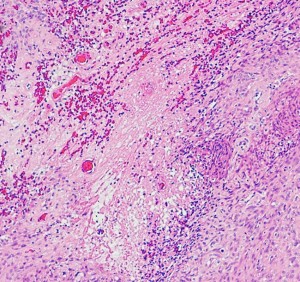

anaplastic meningioma WHO grade 3 退形成性髄膜種

極めて高い細胞密度です。MIB-1は20%に達します。肉腫 sarcoma としての性質を有し,頭蓋内で転移し,摘出しても多発再発します。放射線外科治療でもコントロールすることはできません。